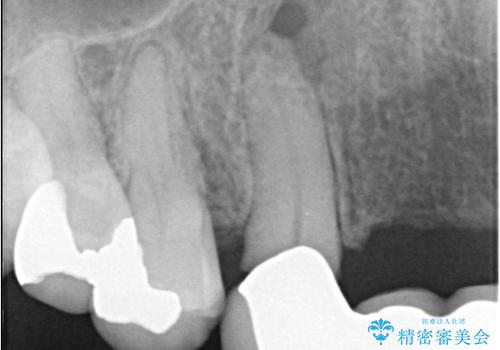

- 歯茎の大きな腫れを主訴に来院された患者様です。前歯5本にはブリッジが装着されていました。レントゲン検査より、右上3番に大きな根尖病巣が認められ、さらに左上1、2番の支台歯にも破折があったため、抜歯を行いました。その後、インプラントを3本埋入し、オールセラミッククラウンのブリッジで補綴しました。

今回のケースでも、しっかりと固定が得られたため、手術は1回で終了し、短期間でオールセラミッククラウンまで装着することができました。患者様も術後の痛みはなく、処方した痛み止めも服用されなかったとのことです。

これだけ大きな病変があったにもかかわらず、痛みがなく短期間で治療が終わったことに加え、被せ物の色も周囲の歯に調和し美しく仕上がったことに、大変ご満足いただけました。